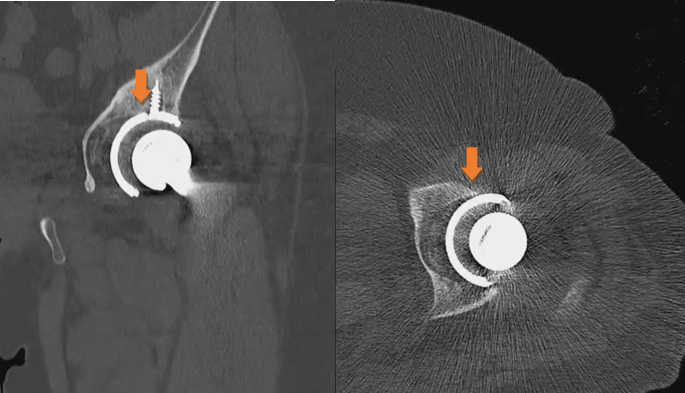

Taking into consideration the short post-operative time, it was decided to avoid any nuclear medicine examination, such as single-photon emission computed tomography (SPECT)-CT or positron emission tomography (PET) to limit the risk of exposure. It is shown that these imaging modalities present lower accuracy in the early post-operative period. Given the fact that there were no signs of infection, early loosening of the THA components was suspected, and so a dynamic radiographic imaging was scheduled to examine the THA prostheses during movement. The examination was undertaken in the radiology department with the equipment of a barium meal gastrointestinal series for high-resolution imaging. The patient was placed in a supine position with the affected limb free and the chest, abdomen, and genitalia of the patient covered with a radioprotective gown. The surgeon passively performed hip flexion, hip extension, internal and external rotation to the extremes of the hip range of motion of the left lower extremity under radiography. The movements were performed in a circular manner, anti-clockwise starting from 60° flexion and internal rotation to full external rotation followed by hip extension. The same movement protocol was followed in 90° flexion and in 100° of hip flexion. Dynamic imaging revealed gross motion of the acetabular cup during passive movements of the hip joint, so the diagnosis of aseptic loosening was established (Fig. 6 and Video 1).

Figure 6: Images during dynamic radiography.

Video 1: Gross motion and instability of the acetabular cup during dynamic radiography.